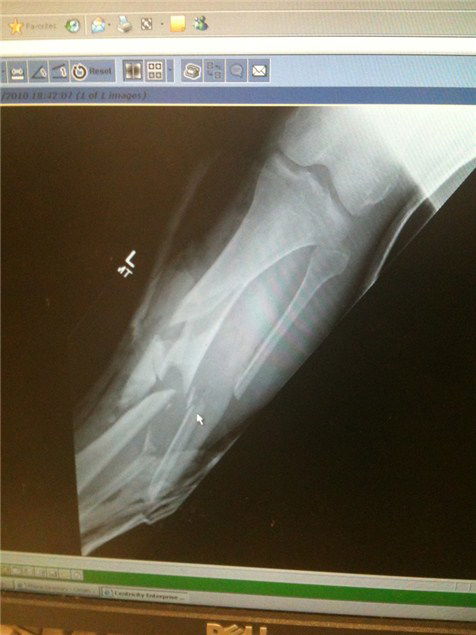

I think Ian Hutchinson was equally nervous. Not only did he have an external fixator cage on his still-broken left, lower leg, it was also only covered up by a piece of fabric and his left foot encased in nothing more than a DC skate shoe. If that wasn’t bad enough his loaned R1 was on brand new rubber and had no back brake hooked up – largely thanks to the fact that he now has to shift gear with his right foot.